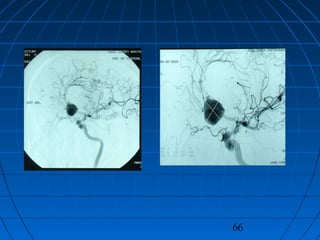

 DÖ: 59 yaşında erkek hastaDÖ: 59 yaşında erkek hasta

 BaşağrısıBaşağrısı (akut şiddetli, son 24 saat(akut şiddetli, son 24 saat

içinde)içinde)

 GKS 14 (WFNS grade 2)GKS 14 (WFNS grade 2)

 Fisher grade IVFisher grade IV

CERRAHİCERRAHİ

 Sol pterional trans-sylvian yaklaşımSol pterional trans-sylvian yaklaşım

 AcomA Anevrizması kliplendiAcomA Anevrizması kliplendi